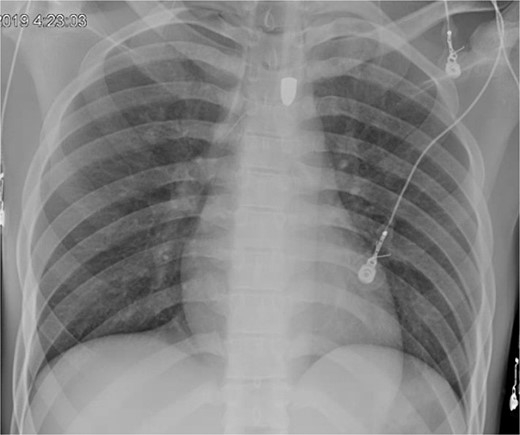

A repeat otolaryngology endoscopy exam on HD 2 revealed a 1.5 cm wound in the posterior pharyngeal wall, confirming the suspicion that the bullet entered the posterior of the mouth, was swallowed, and was now migrating down the GI tract. Serial X-rays tracked its transit (Fig. 4). Despite treatment, his condition remained critical. He underwent tracheostomy, gastrostomy, and diaphragmatic pacemaker placement. The patient was discharged to a long-term care facility on HD 22 but succumbed to complications from AIDS and pneumonia months later.